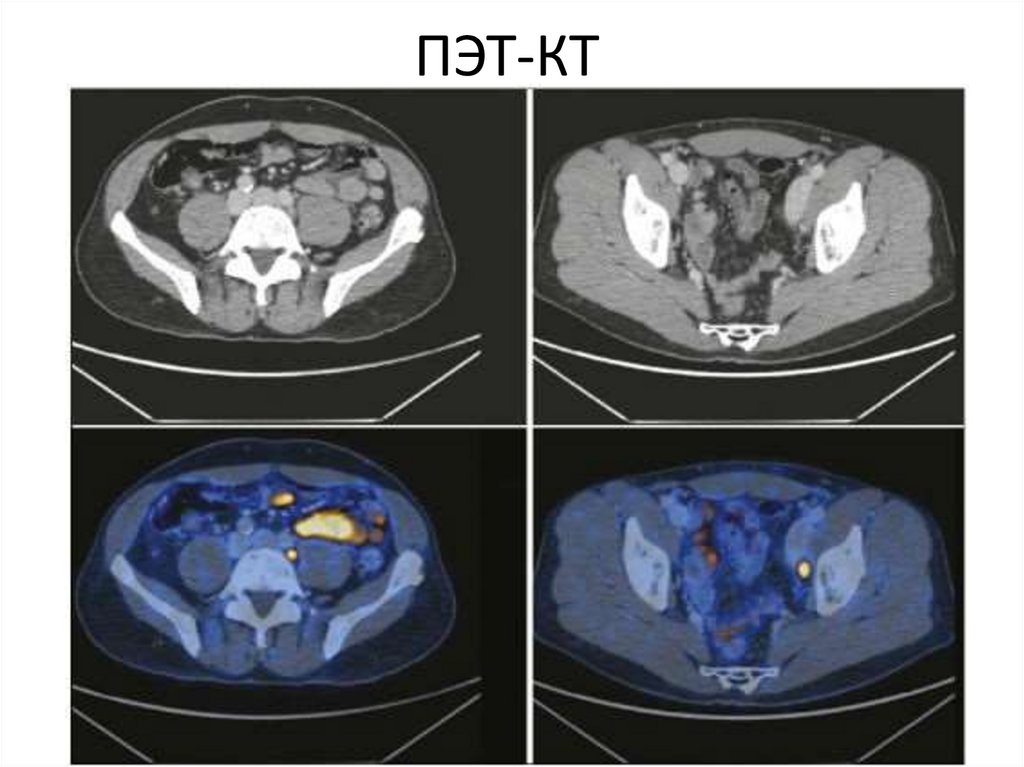

Позитронно-эмиссионная томография

ПЭТ-КТ